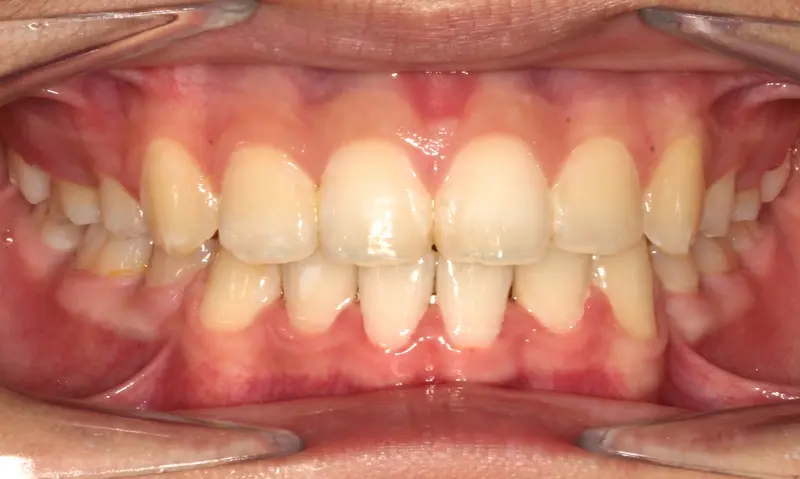

After treatment: The Expansion Phase

After

Before treatment: The Expansion Phase

Before

Severe crowding with blocked-out permanent teeth. The jaw size was insufficient to accommodate the erupting adult teeth, leading to significant rotation and displacement.

By intervening early, we utilized rapid palatal expansion to develop the arch width. This created the necessary space for the permanent teeth to erupt naturally, avoiding the need for future extractions.